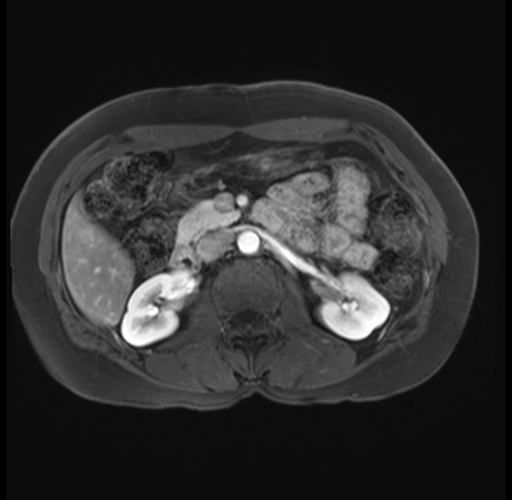

Imaging Analysis

Look through the patient's CT scan to identify any areas of concern for the necessary procedure.

Based on your CT findings, which issue(s) are present and would give reason for "planned slowing down moment(s)" in this case?

Considering a standard distal pancreatectomy procedure, what step(s) of the operation would you do differently in this case?